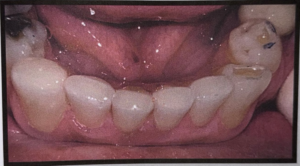

Deep, Discoloured Grooves on Your Lower Front Teeth — Class 6 Incisal Wear

Class 6 incisal wear describes the deep, discoloured grooves that develop along the biting edges of lower front teeth. What begins as surface discolouration becomes a hollow trough through the enamel and into the dentine beneath, leaving a thin, fragile enamel rim that is increasingly prone to decay and fracture.